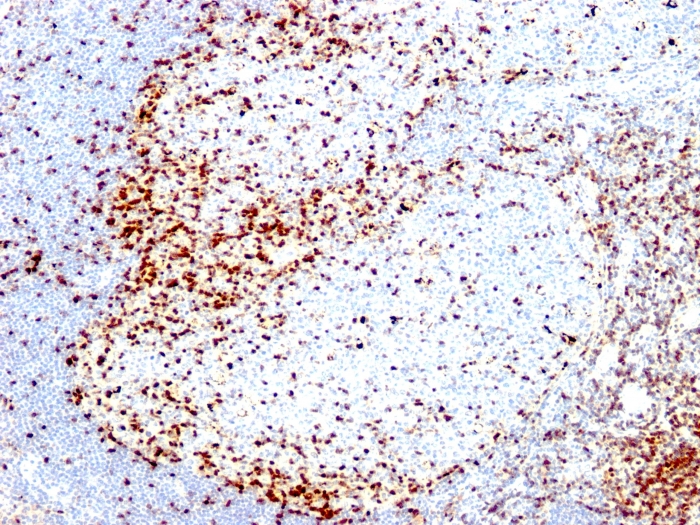

IHC-P analysis of human tonsil tissue using GTX35177 ZAP70 antibody [2F3.2].